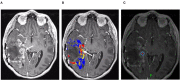

In the follow-up treatment of high-grade gliomas (HGGs), differentiating true tumor progression from treatment-related effects, such as pseudoprogression and radiation necrosis, presents an ongoing clinical challenge. Conventional MRI with and without intravenous contrast serves as the clinical benchmark for the posttreatment surveillance imaging of HGG. However, many advanced imaging techniques have shown promise in helping better delineate the findings in indeterminate scenarios, as posttreatment effects can often mimic true tumor progression on conventional imaging. These challenges are further confounded by the histologic admixture that can commonly occur between tumor growth and treatment-related effects within the posttreatment bed. This review discusses the current practices in the surveillance imaging of HGG and the role of advanced imaging techniques, including perfusion MRI and metabolic MRI.